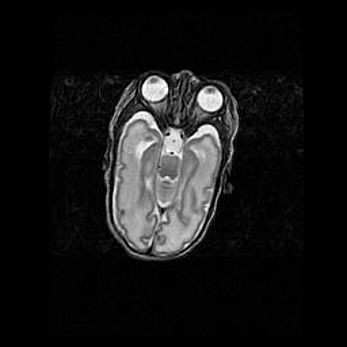

Сообщающаяся гидроцефалия. Кистозная энцефаломаляция головного мозга.

Возраст: 3 месяца 4 дня

Вес: 3100 г

Пол: женский

Окружность головы: 34 см

Срок гестации: 31 неделя

Кистозная энцефаломаляция головного мозга - одна из форм поражения головного мозга в детском возрасте. Характеризуется возникновением множественных и распространённых кист в коре, белом веществе и подкорковых образованиях головного мозга у плодов, новорождённых и детей раннего возраста. Развитие кистозной энцефаломаляции связано с внутриутробной асфиксией и гипотонией, родовой травмой, тромбозом синусов, пороками развития сосудов, инфекциями, сепсисом и другими причинами. Наиболее значимые инфекционные агенты: вирусы простого герпеса, цитомегалии, краснухи, токсоплазмы, энтеробактерии, золотистый стафилококк и другие.